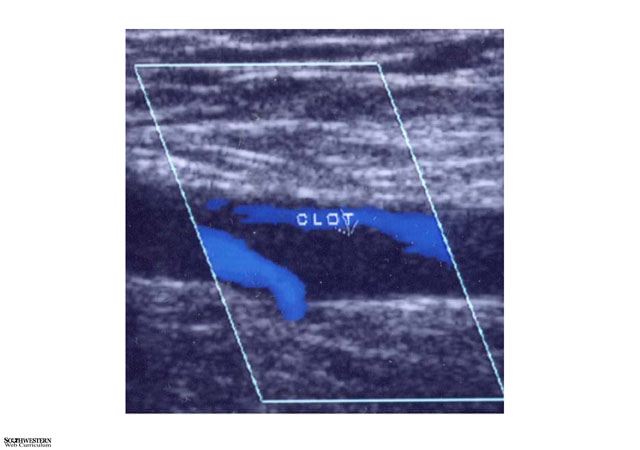

VASCULAR SURGERY  Case #1 - A 58 year old with a swollen leg    No previous image Go to next image

Sonographic scan showing clot in vein